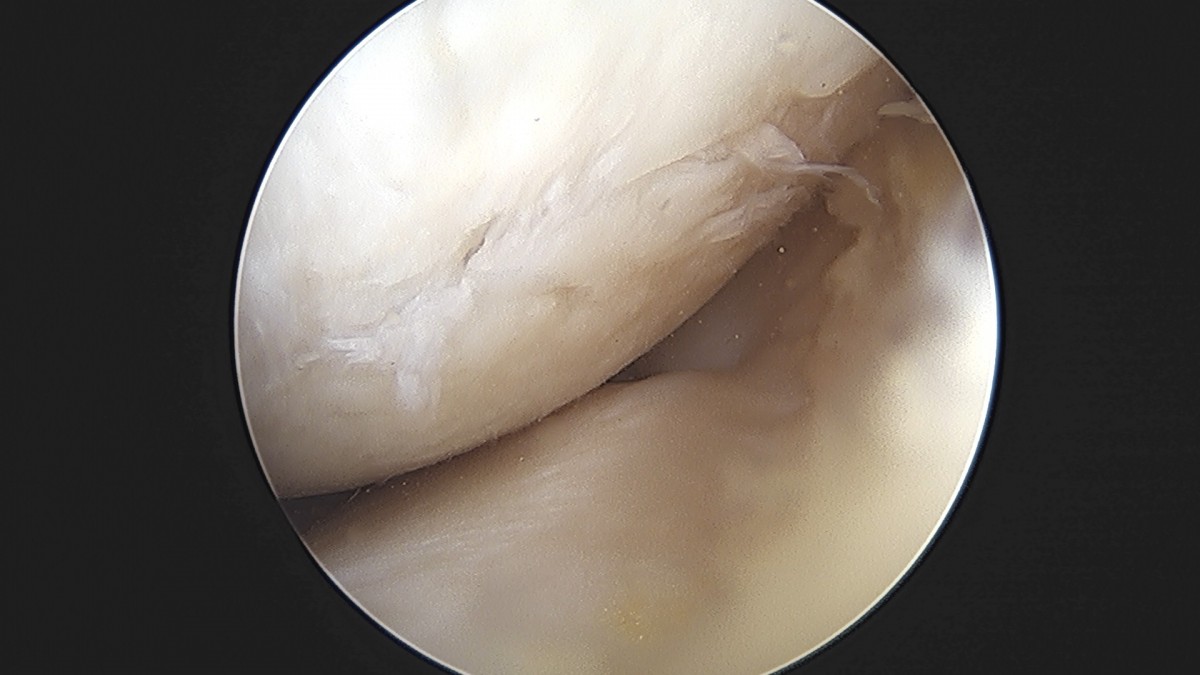

이재상원장님 무릎 반월상 연골판 절제술 박강O 환자

dae765e4d9ac96aee867c9d6292d8784_1758005268_7537.jpg